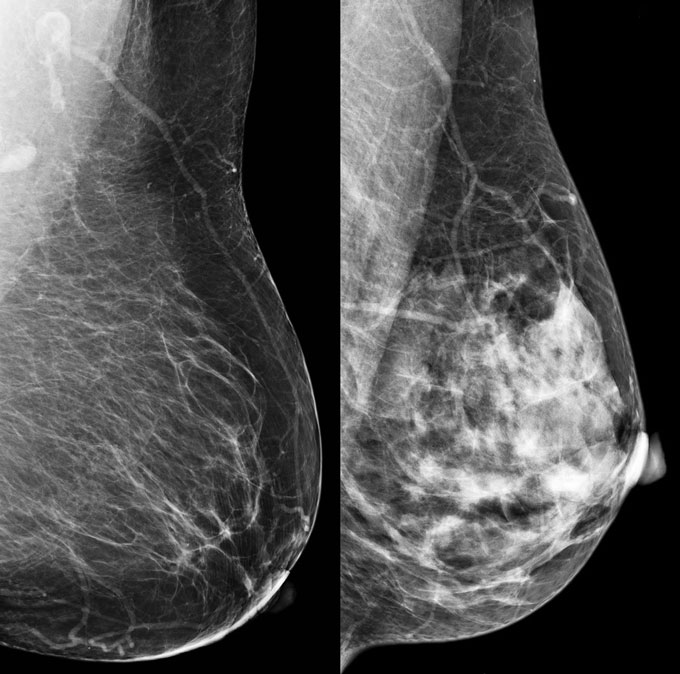

A radiologist visually assesses the density of breast tissue from a mammogram. The two non-dense classifications are “almost entirely fatty” and “scattered areas of fibroglandular density,” which means mainly fatty tissue with some areas of dense tissue. Around 8 and 46 percent of U.S. women ages 40 to 79 have those two classifications, respectively.

Dense breasts pose two problems. First, on a mammogram, glandular and connective tissue show up as white — which is how tumors or other abnormal breast tissue look too. So dense tissue could hide the very things a radiologist is looking for.